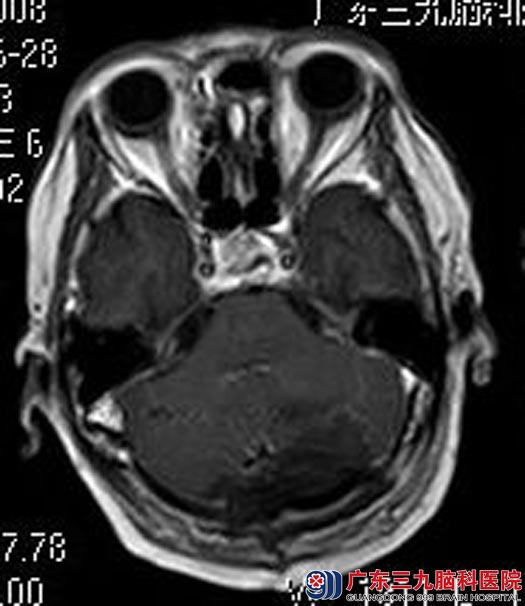

完善术前检查后,由鲁明主任主刀,在全麻下行左侧跨小脑幕脑膜瘤切除术,术中显微镜下见肿瘤质地较软,血供一般,予镜下全切肿瘤,手术非常顺利。术后江奶奶恢复得很好,十天后即康复出院。术后病理结果提示:纤维型脑膜瘤(WHO I级)。

▲手术后